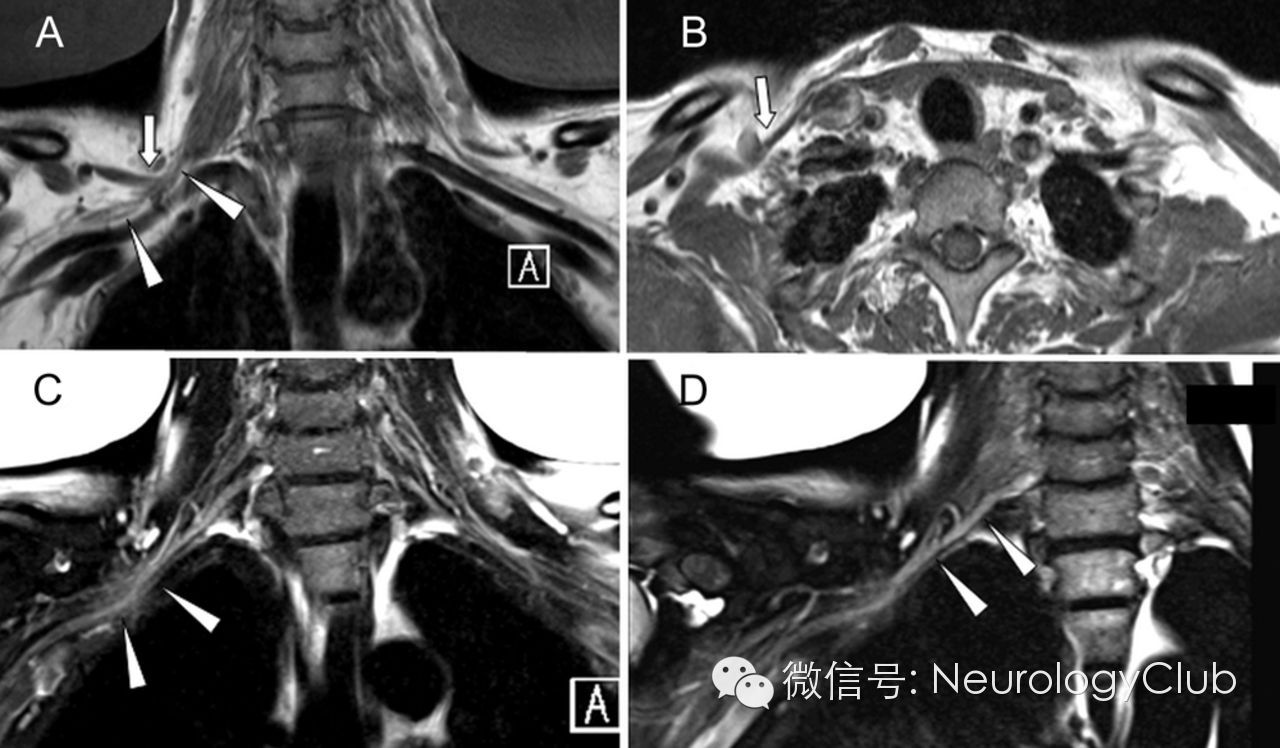

64岁男性,诉右侧颈部和手臂疼痛5月,随后出现进行性手无力。颈部X线及磁共振正常。肌电图提示下段臂丛病变。磁共振神经成像见纤维带压迫引起的右侧臂丛扭曲伴C8神经根增厚。患者拒绝手术。

(A-B:T1WI;C-D:T2WI;A-B:箭示一厚纤维带;A、C:箭头示扭曲和水肿的臂丛神经;D:斜冠状位箭头示C8神经根选择性增厚)